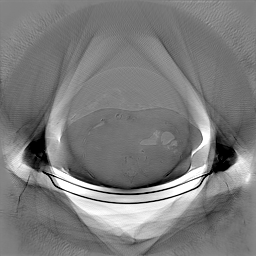

Classical diffusion models reconstruct images by progressively denoising from an initial Gaussian noise image, a process that inherently introduces uncertainty due to random noise initialization. In contrast, I2SB directly learns a diffusion bridge between two sample distributions, effectively bypassing the need for random noise sampling and thereby reducing reconstruction variability.

To assess the uncertainty of our method, we performed multiple reconstructions using different random seeds. As shown in Fig. 3, the ground truth and representative sampled images are presented in Fig. 3(a) and (b–d), respectively. The mean reconstruction and pixel-wise standard deviation across runs are displayed in Fig. 3(e) and (f). Only minimal differences are observed between reconstructions, indicating that I2SB produces highly consistent results. These findings confirm that, compared with classical diffusion models, I2SB substantially reduces uncertainty across repeated reconstructions.